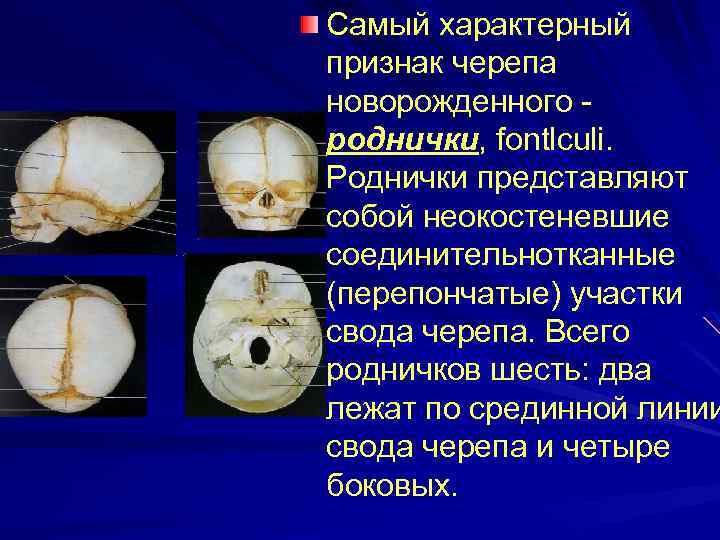

Анатомия детского черепа: Рентгеновские снимки и описание